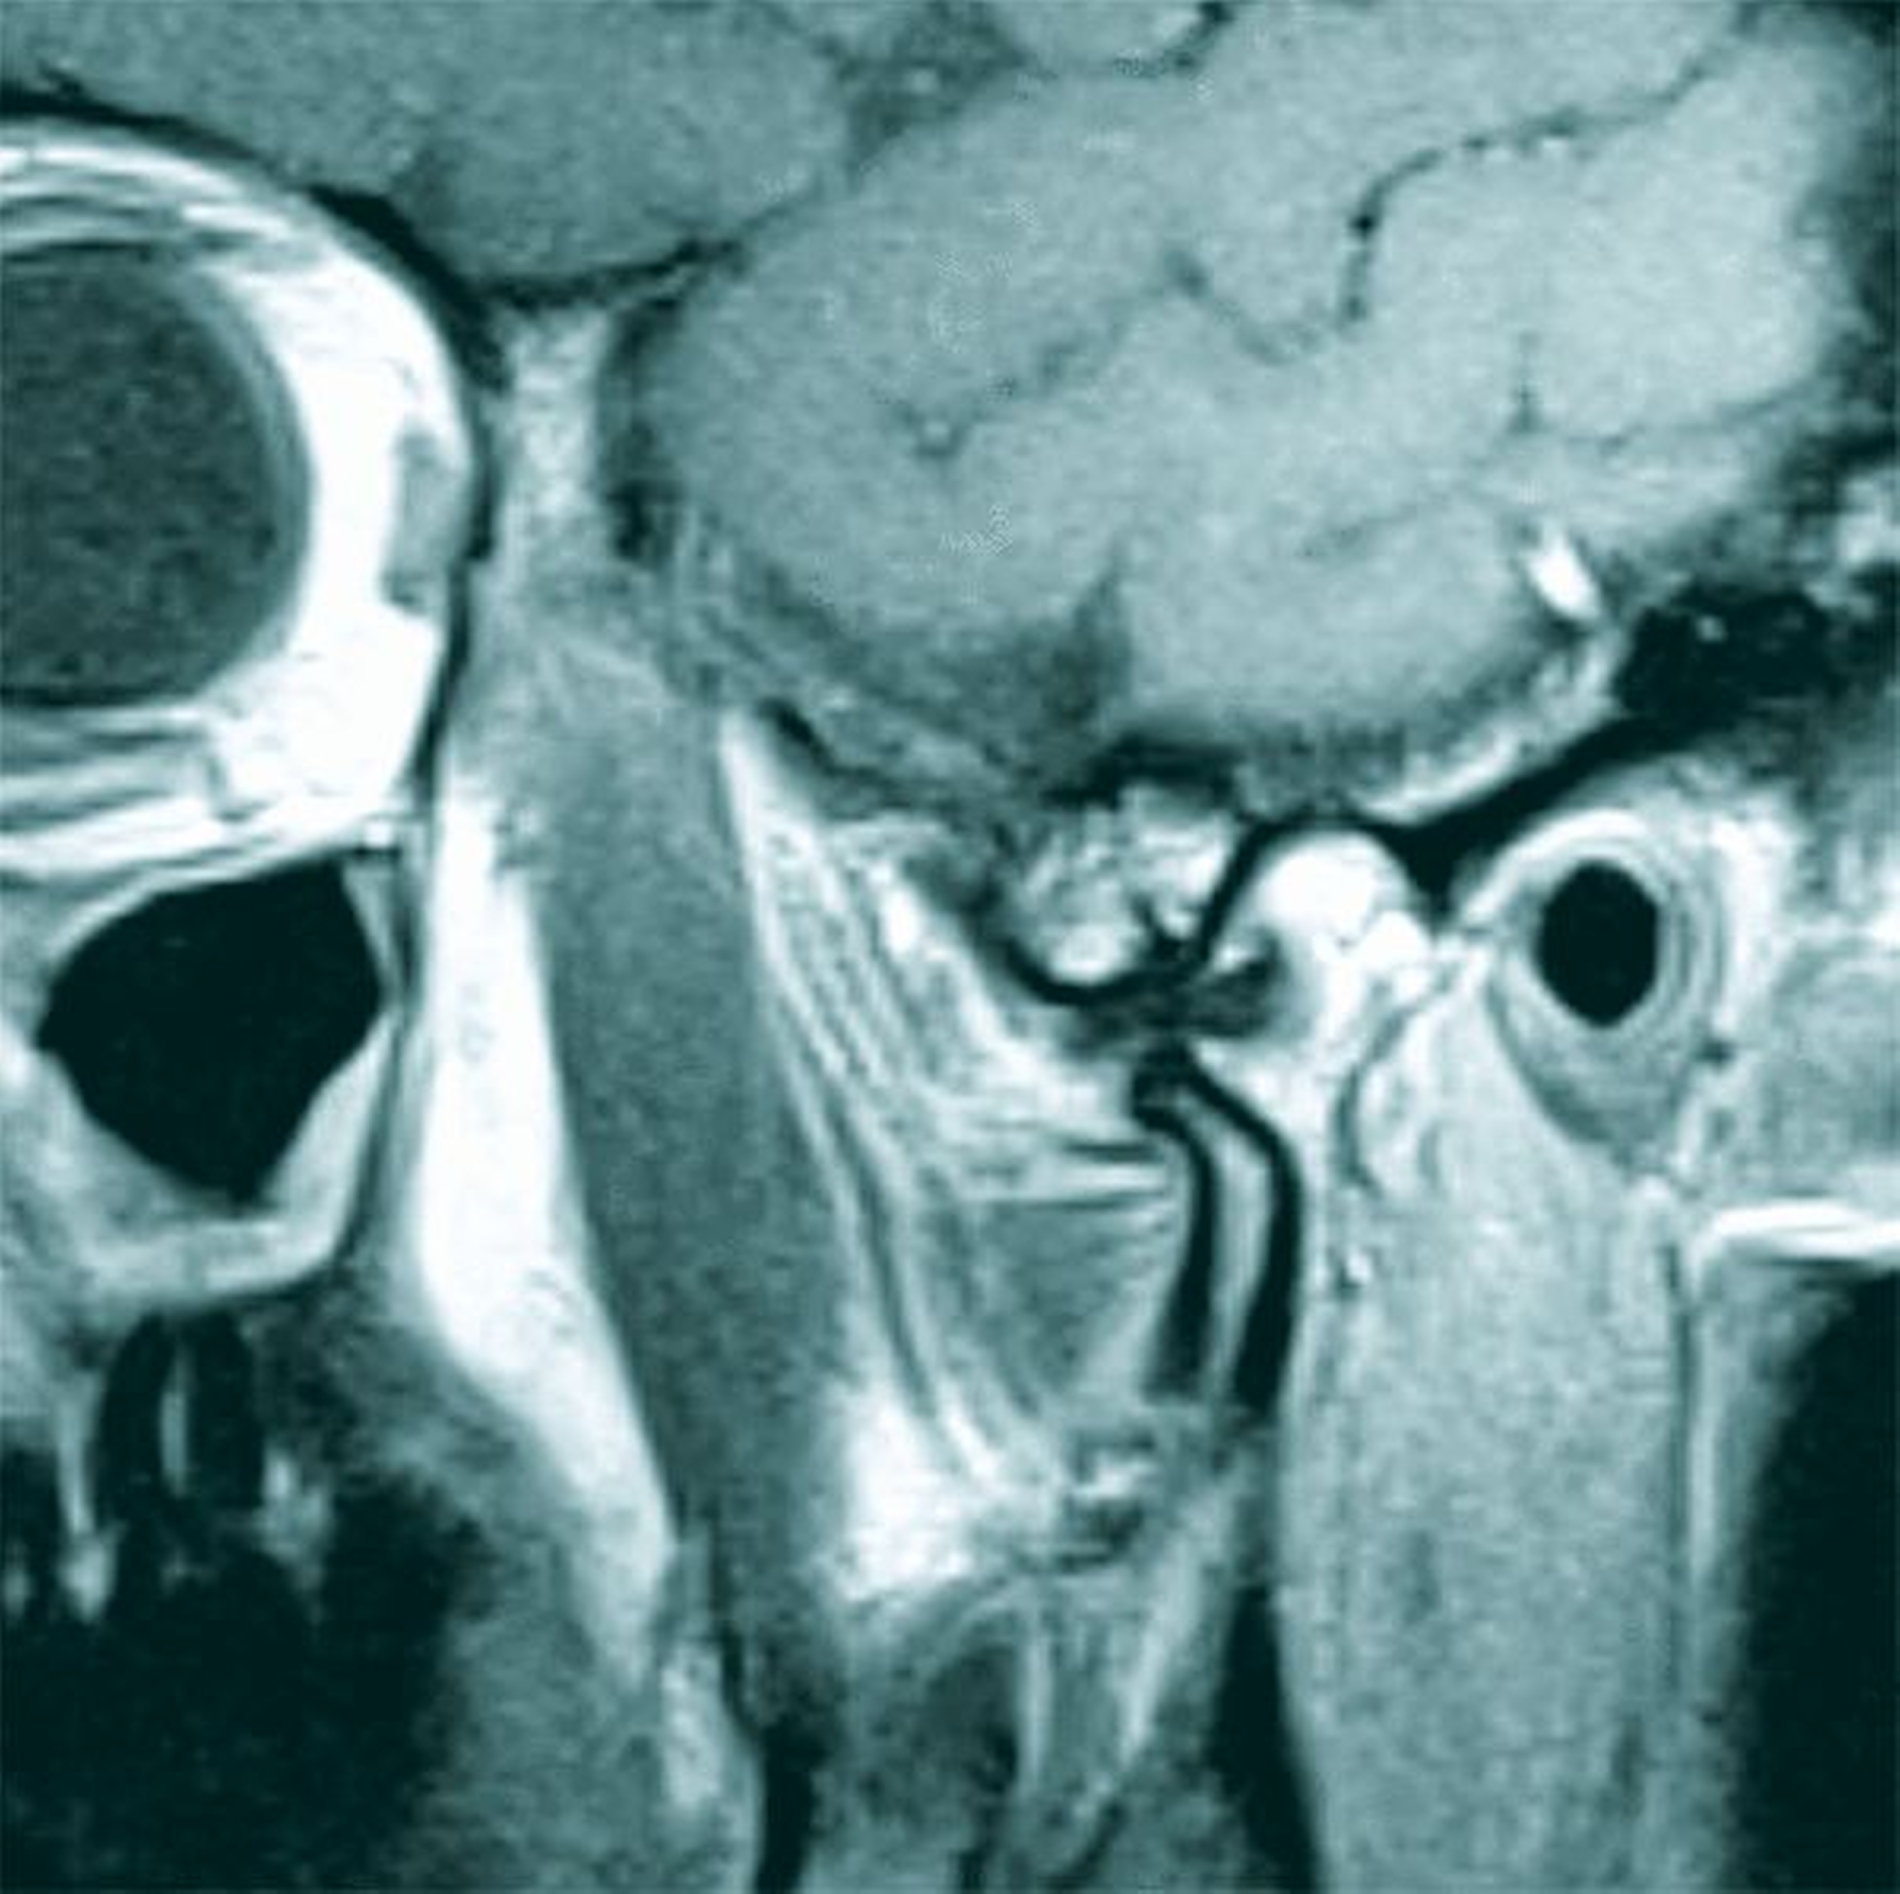

Neben der klinischen Untersuchung wurden eine digitale Volumentomografie (DVT) zum Ausschluss einer knöchernen Veränderung und eine Magnetresonanztomografie (MRT) der Kiefergelenke mit dynamischer Bildsequenz in Funktion angefertigt. Während sich die knöcherne Situation unauffällig mit einem normalweiten Gelenkspalt und normal konturiertem Kiefergelenk darstellte (Abbildung 2), zeigte sich in der MRT eine anteriore Diskuseinklemmung am rechten Kiefergelenk ohne Reposition (Abbildung 3). Der Diskus wies keine ausgeprägten Destruktionszeichen auf, wobei ein moderates Kiefergelenksödem rechts, bildmorphologisch passend zu einer beginnenden Arthritis, zu beobachten war.